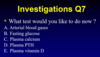

What Ix do you do for calcium renal stones?

- CT-KUB

- Stone analysis

- Urine and serum biochemistry